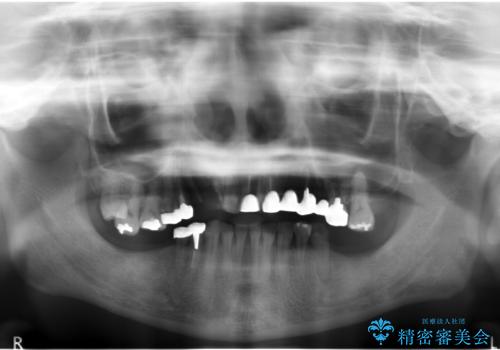

- 3年6ヶ月

- 30回以上

- 痛くて噛めない、これまでだましだまし治療をしてきたがこれを機にすべてきっちりと治したい、口の中の悩みを解決したいと来院されました。

抜歯や歯周病治療、欠損補綴を含め、全顎的な治療を計画・提案します。

口腔内に歯の破折や歯周病、虫歯、欠損など複数の問題が存在する場合局所的に問題を解決していくのではなく全顎的な治療を行っていくことで長期的な予後を見込むことができます。